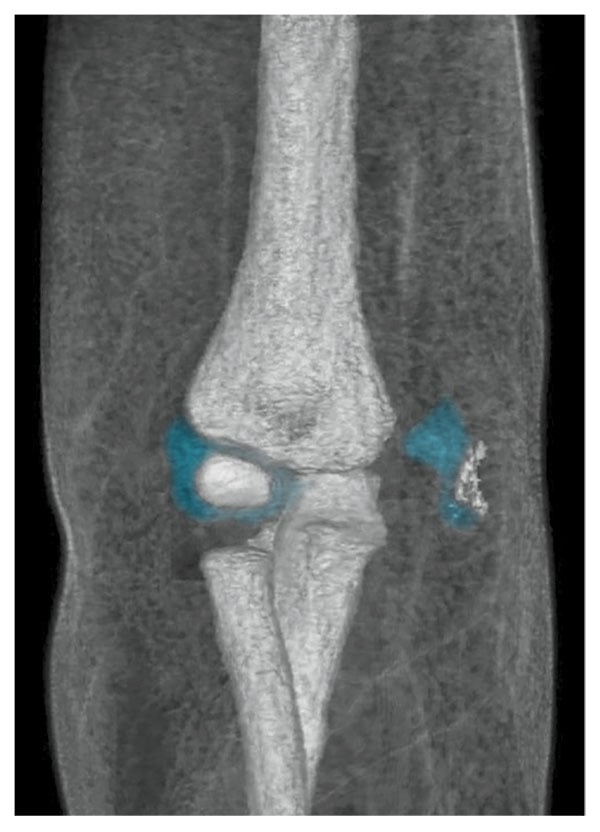

Fractures of the elbow are a common injury in children. Supracondylar humeral fractures are the most prevalent type of elbow fracture, whereas lateral condyle fractures are less common, and medial epicondyle are the least common.1 In children, medial epicondyle ossification occurs between ages 3 and 7 years.2 When a pediatric patient presents with elbow pain and decreased range of motion, a radiographic examination commonly is performed. However, because elbow fractures involving the unossified distal humerus might not be evident using this modality, other imaging examinations, such as magnetic resonance (MR) imaging, should be performed whenever a fracture is suspected. MR imaging can detect bone fractures as well as injury to surrounding anatomy such as cartilage, tendons, and ligaments. This case summary discusses a 2-year-old patient with a fracture of the distal humerus where the unossified cartilaginous trochlear and medial epicondyle fracture fragment was displaced from the joint. (see Figure 1).